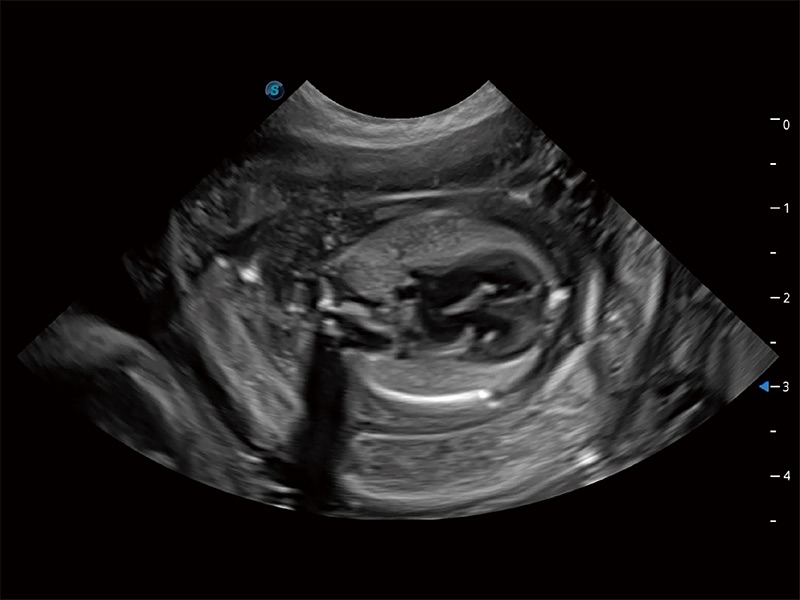

动物是人类最亲密的朋友和最值得信赖的伙伴。竞技宝(JJB)官方网站也一直致力于探索动物专用的超声影像解决方案。全新推出的ProPet系列,是竞技宝(JJB)官方网站在动物超声影像智能化、专业化、精准化的一次跨越式革新。动物不能用言语来表述自己的不适,通过超声影像,ProPet系列搭建了动物医生与不同物种沟通的“桥梁”,为动物医生注入了“治愈之力”。 ProPet 80 是竞技宝(JJB)官方网站匠心打造的一款高端动物专用彩超,采用性能卓越的全新硬件架构,极大提升超声系统的运行效率和数据处理能力,帮助动物医生从容应对日益增多的挑战性病例和日益多样化的临床需求。

高性能和先进的临床应用工具可以为动物医生提供临床信心。ProPet 80 搭载了先进的腹部和浅表应用工具,帮助医生在日常临床实践中发挥前所未有的作用。

ProPet 80 专为动物医生设计,对不同的动物体型和生理结构作出了针对性的优化。通过动物影像专用软件,可满足个性化的应用需求,帮助动物医生获得更精确的诊断数据。

ProPet 80 全新的动物超声智能软件和丰富的探头群,为动物医生提供了高清晰度和精细分辨率的图像,无论在宠物、马科、畜牧还是实验室动物等应用中都可以轻松应对,为您的日常工作带来满意的体验。